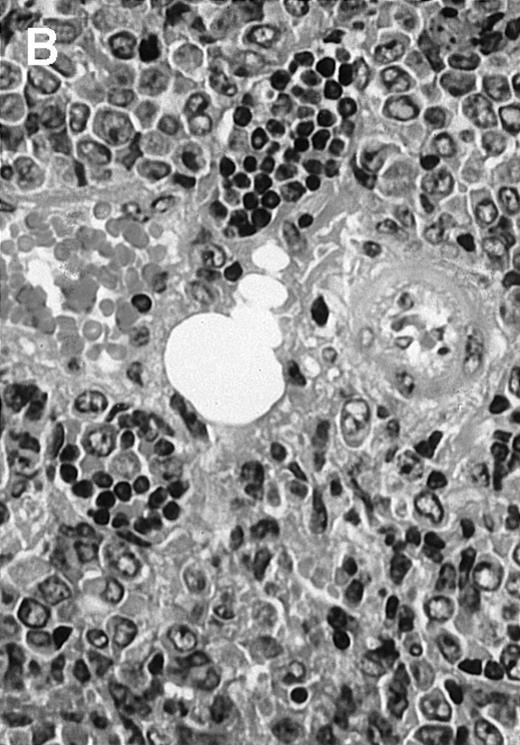

To explore the mechanisms of the protection from BCL growth, histologic analysis was performed on tumor tissue from mice treated with ST40L, ST, or PBS alone. In the mice treated with PBS alone, no cellular infiltrate expressing FasL was observed in the surrounding tissues and inside the BCL region (Figure 4A and D). In contrast, infiltrating lymphocytes expressing FasL were observed around the vessels and also scattered in the smaller tumor tissues in the mice treated with ST (Figure 4B and E). Small hard nodules (2-5 mm in diameter) were observed at the SC injection sites of the long-term survival mice that had been treated with ST40L. On histologic analysis, these small nodules were confirmed to be the result of an accumulation of lymphocytes, and not BCL cells (Figure 4C). These lymphocytes were also found to be strongly positive for FasL expression (Figure 4F). On the other hand, lymphocytes infiltrating in the nodules were stained by either CD4+ Ab or CD8+ Ab, but the ratio of CD4+ and CD8+ cells was not 1-sided (data not shown).

Histologic analysis of A20 tumors excised 21 days postchallenge from BALB/c mice immunized with ST40L.

(A) HE stain of a BCL region in a mouse treated with PBS alone. (B) HE stain of a smaller BCL region in a mouse treated with ST. (C) HE stain of a small hard nodule at the SC injection site in a mouse treated with ST40L. (D) Fas ligand staining of a BCL region in a mouse treated with PBS alone. (E) Fas ligand staining of a BCL region in a mouse treated with ST. (F) Fas ligand staining of a small hard nodule at the SC injection site in a mouse treated with ST40L. Original magnifications are ×400.